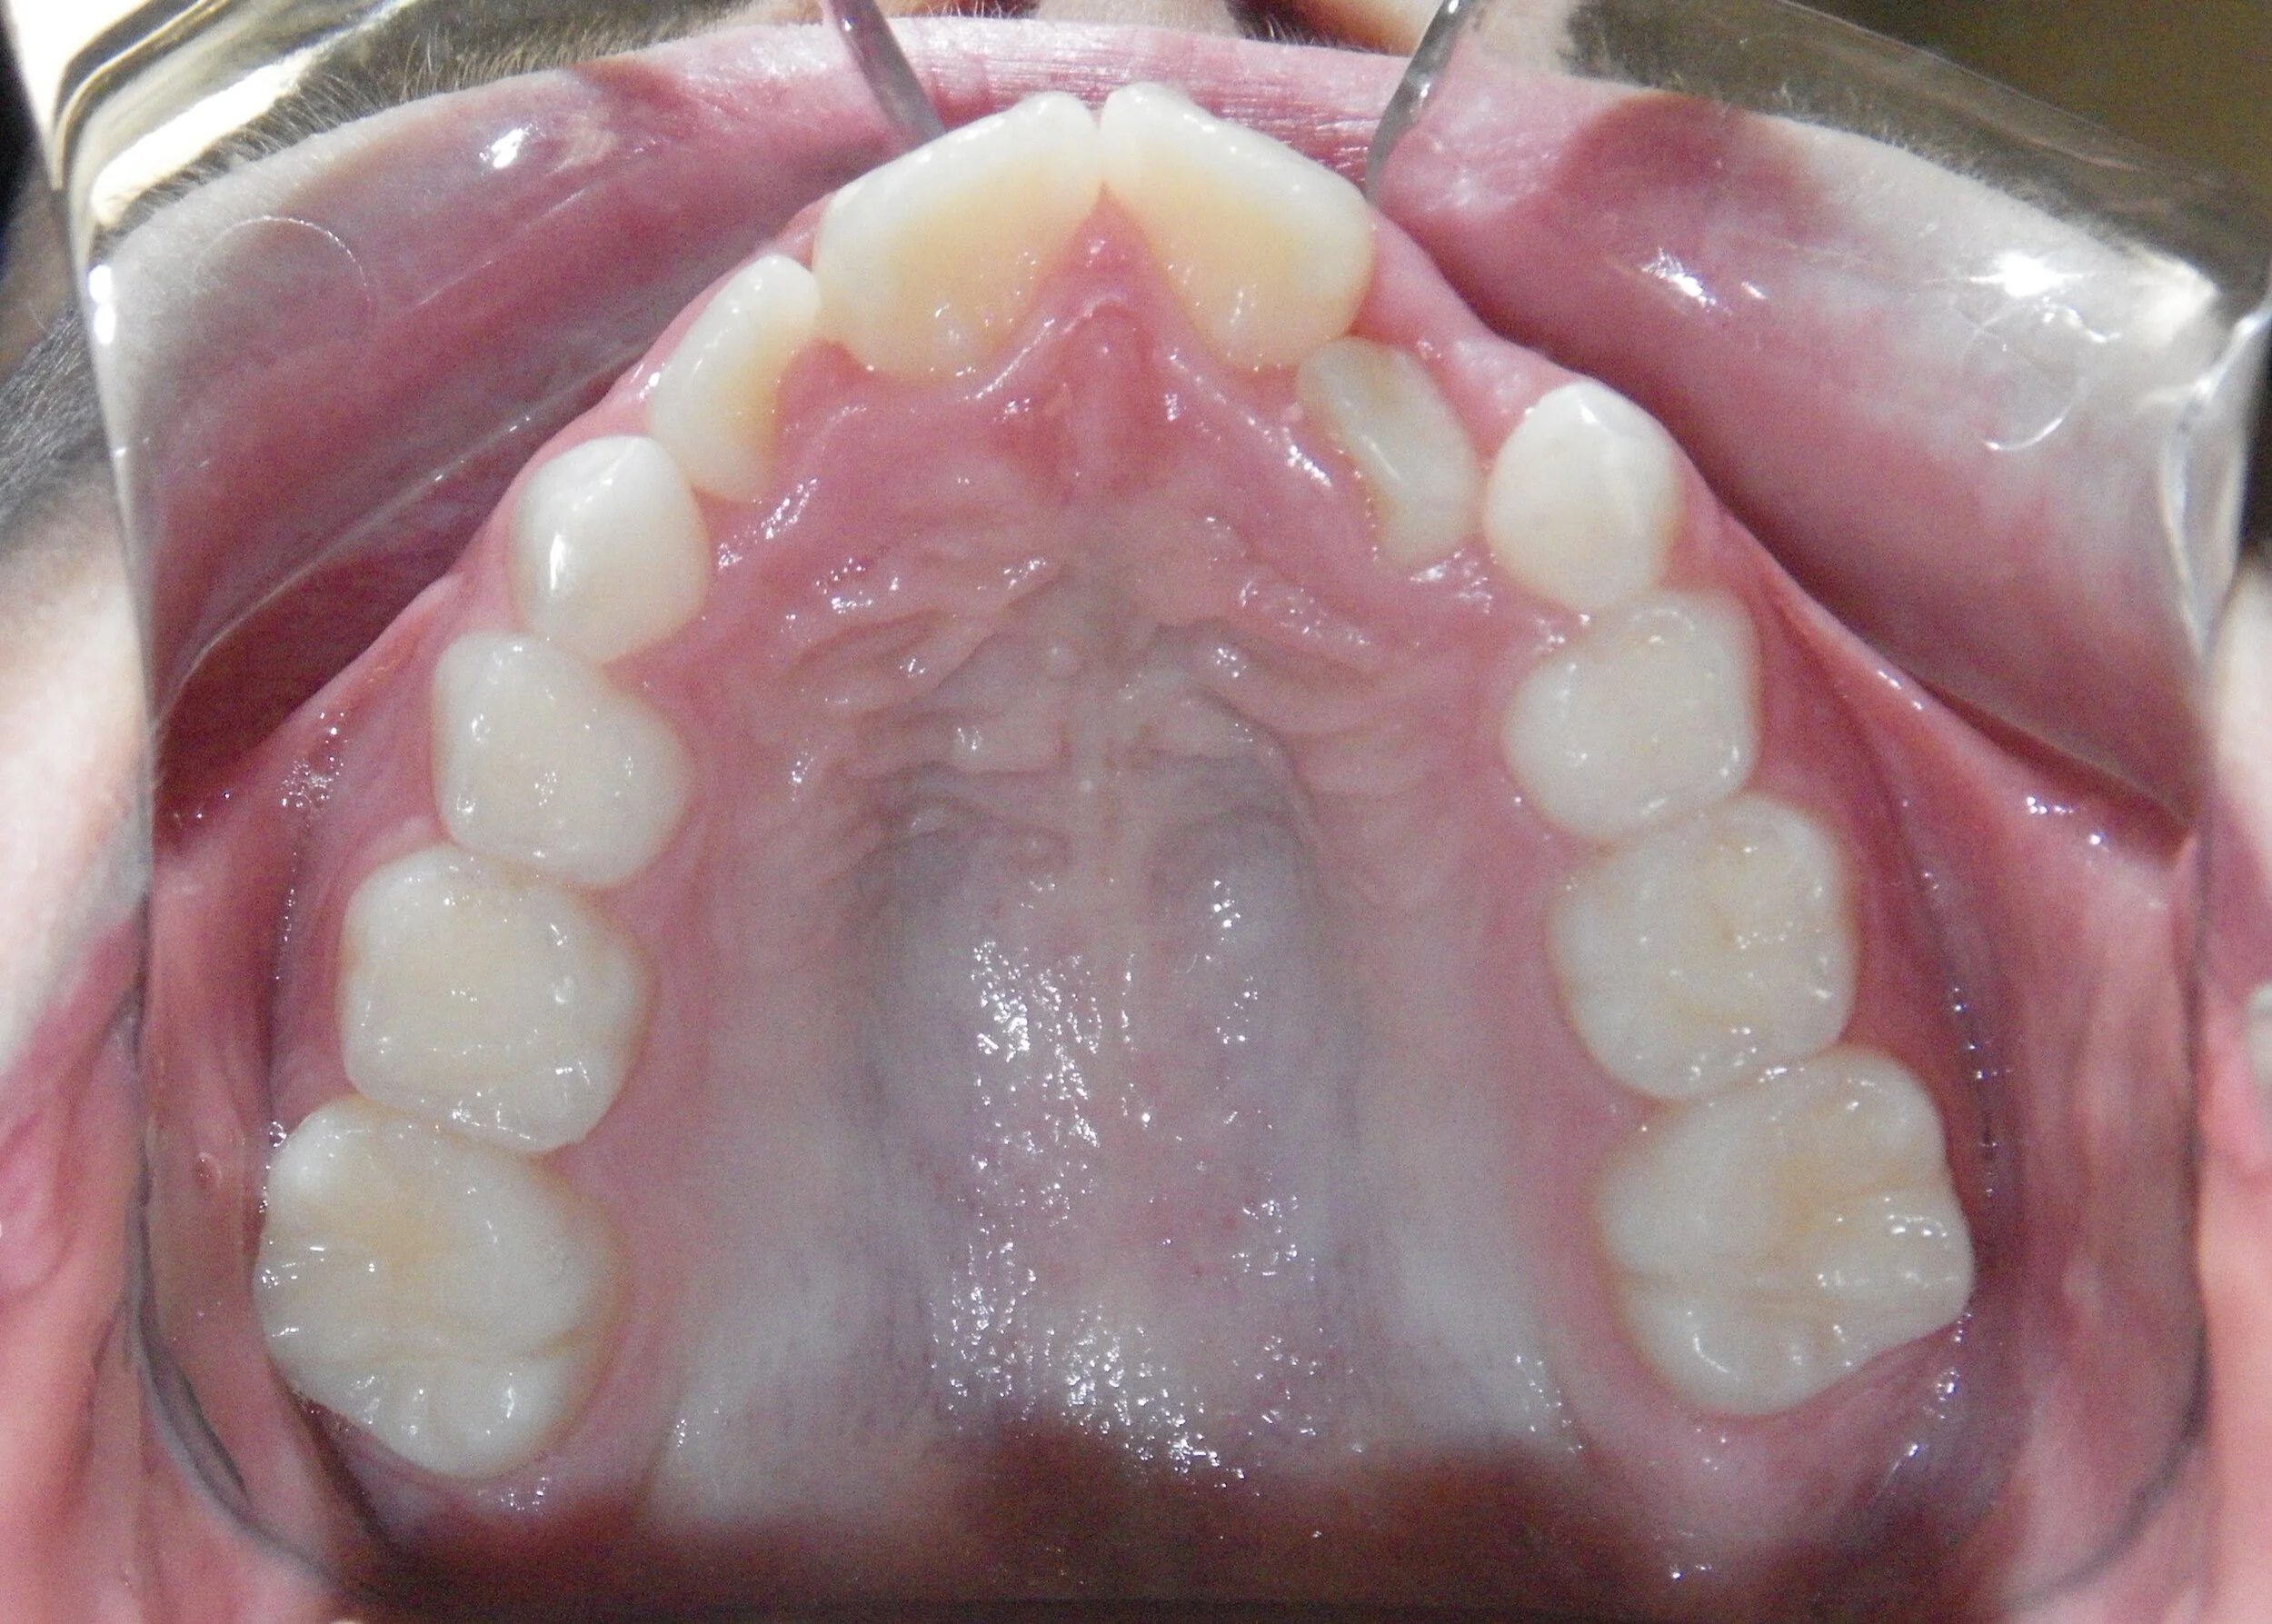

Phase I can be used to help change unfavorable growth or to make room so all the adult teeth have room to erupt. Here, we used Phase I to make room for the adult canines and followed up with Phase II treatment to a get a great esthetic and functional result!